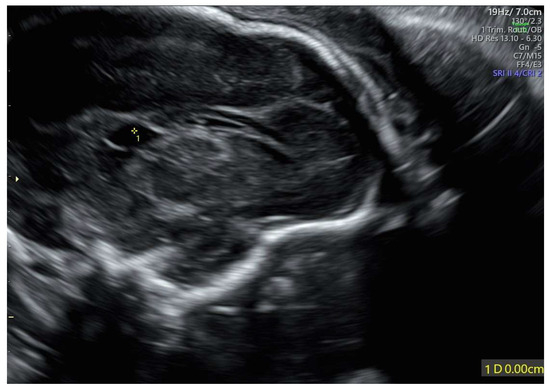

Background: The purpose of this study was to examine the relationship between qualitative characteristics and quantitative parameters from contrast-enhanced ultrasound (CEUS) and microvessel density (MVD) in hepatoblastoma (HB), as well as to investi...